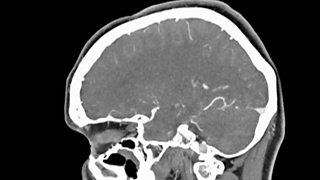

Katharine Carpenter reveals why getting a diagnosis for dementia is a lottery.